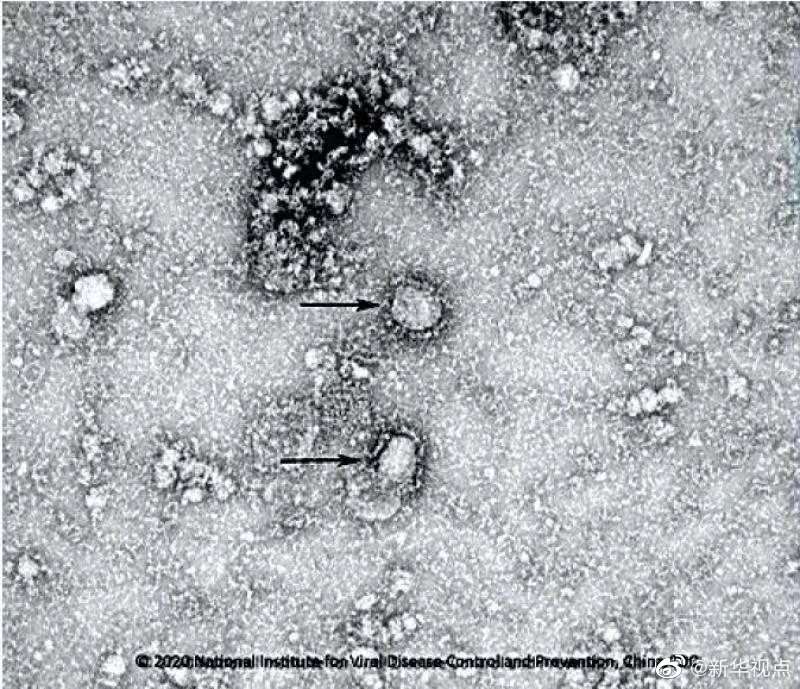

好消息!中國疾控中心成功分離我國首株新型冠狀病毒毒種,它長這樣!

國家病原微生物資源庫于2020年1月24日發布了由中國疾病預防控制中心病毒病預防控制所成功分離的我國第一株病毒毒種信息及其電鏡照片、新型冠狀病毒核酸檢測引物和探針序列等國內首次發布的重要權威信息,并提供共享服務。看病毒“真容”↓↓↓(記者田曉航、王秉陽)